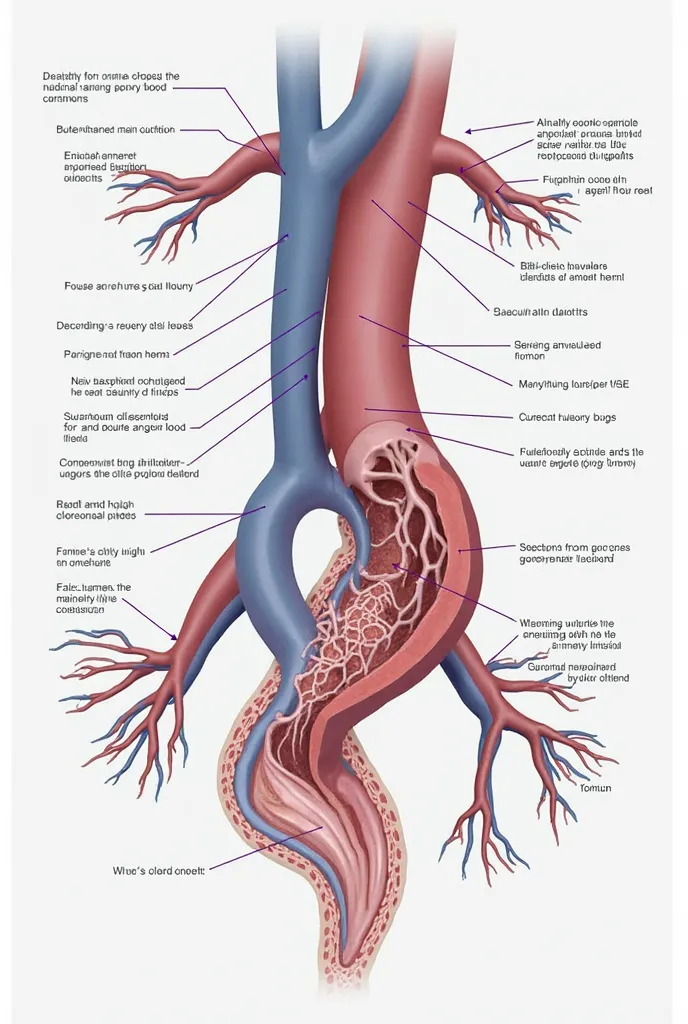

A diagram of the anatomy of the human body